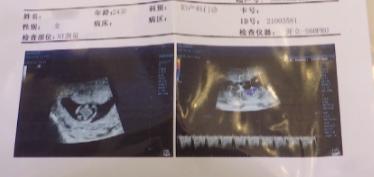

李先生:我說要不要選擇把娃娃打了?你不想結(jié)婚。她不打,她說她第一次懷孕,一定要生下來。因?yàn)樗莻老師,不能未婚先育,所以現(xiàn)在必須馬上領(lǐng)證。

李先生:我不同意,因?yàn)槲覀兪?/span>奉子成婚,然后她又要做丁克一族,我肯定就懷疑,她打孩子的原因。

李先生:她說法庭上見,說回不去了。她說沒有回旋余地,她已經(jīng)把娃娃私自流產(chǎn)了。